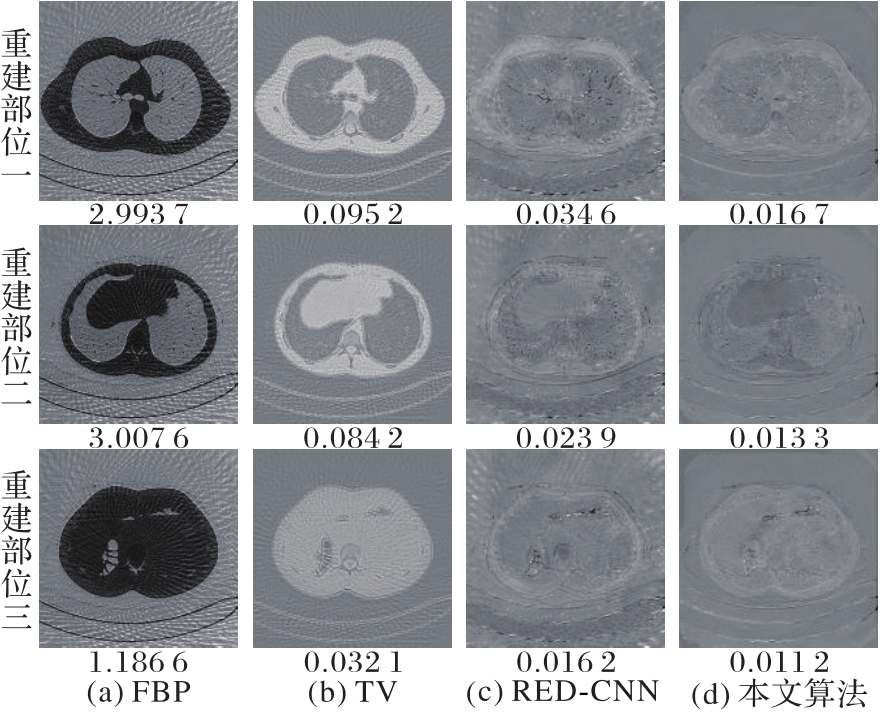

针对采用时域滤波器解析重建后图像存在伪影和图像细节丢失等问题,提出了一种基于卷积神经网络(CNN)的时频域计算机断层扫描(CT)重建算法。首先,在频域中构建了基于卷积神经网络的滤波器网络,实现投影数据的频域滤波;其次,利用反投影操作算子对频域滤波后结果进行域转换得到重建图像;接着,在图像域构建网络对来自反投影层的图像进行处理;最后,在采用最小均方误差损失函数基础上引入多尺度结构相似度损失函数组成复合损失函数,减轻神经网络对结果图像的模糊效应,保留重建图像细节。图像域网络和投影域滤波网络联合作用,最终得到重建结果。在临床数据集上验证了所提算法的有效性,相较于滤波反投影(FBP)算法、全变分(TV)算法及图像域残差编解码CNN(RED-CNN)算法,当投影数目分别为180和90时,所提算法重建结果图像信噪比(PSNR)和结构相似度(SSIM)最高,且归一化均方根误差(NMSE)最小;当投影数目为360时,所提算法仅次于TV算法。实验结果表明,所提算法可以提高CT图像重建图像质量,是一种可行且有效的方法。

| 算法 | 投影数目为360 | 投影数目为180 | 投影数目为90 | ||||||

| PSNR/dB | SSIM | NMSE | PSNR/dB | SSIM | NMSE | PSNR/dB | SSIM | NMSE | |

| FBP | 15.167 9±0.801 9 | 0.277 0±0.016 0 | 0.721 9±0.218 7 | 12.126 7±0.601 2 | 0.200 2±0.014 4 | 1.441 9±0.397 0 | 9.468 6±0.539 0 | 0.147 2±0.015 3 | 2.643 6±0.703 1 |

| TV | 35.954 3±1.207 5 | 0.889 5±0.013 6 | 0.005 9±0.001 4 | 32.259 1±1.408 6 | 0.835 2±0.018 5 | 0.013 9±0.004 2 | 26.268 6±1.352 7 | 0.732 4±0.021 5 | 0.055 8±0.017 8 |

| RED-CNN | 34.176 9±1.146 1 | 0.827 9±0.022 8 | 0.009 0±0.003 0 | 31.347 0±0.628 7 | 0.738 3±0.013 1 | 0.017 3±0.004 8 | 28.944 5±1.800 8 | 0.661 9±0.045 5 | 0.034 4±0.034 7 |

| 本文算法 | 35.505 9±1.129 3 | 0.865 4±0.020 7 | 0.006 5±0.001 6 | 34.267 1±0.779 4 | 0.845 4±0.025 2 | 0.008 7±0.002 3 | 32.119 3±0.677 4 | 0.770 8±0.022 8 | 0.014 2±0.003 3 |

表2 不同算法测试集上指标对比

Tab. 2 Index comparison of different comparison algorithms under different projections